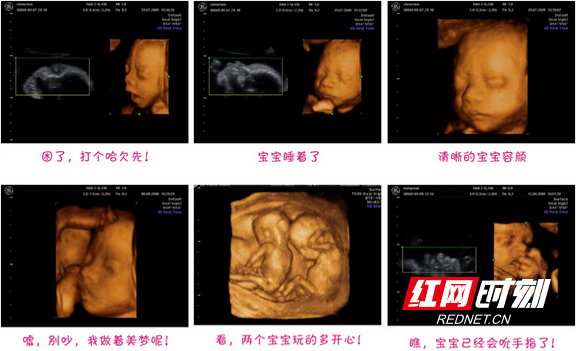

b超中的胎宝宝,千姿百态好可爱__网易亲子